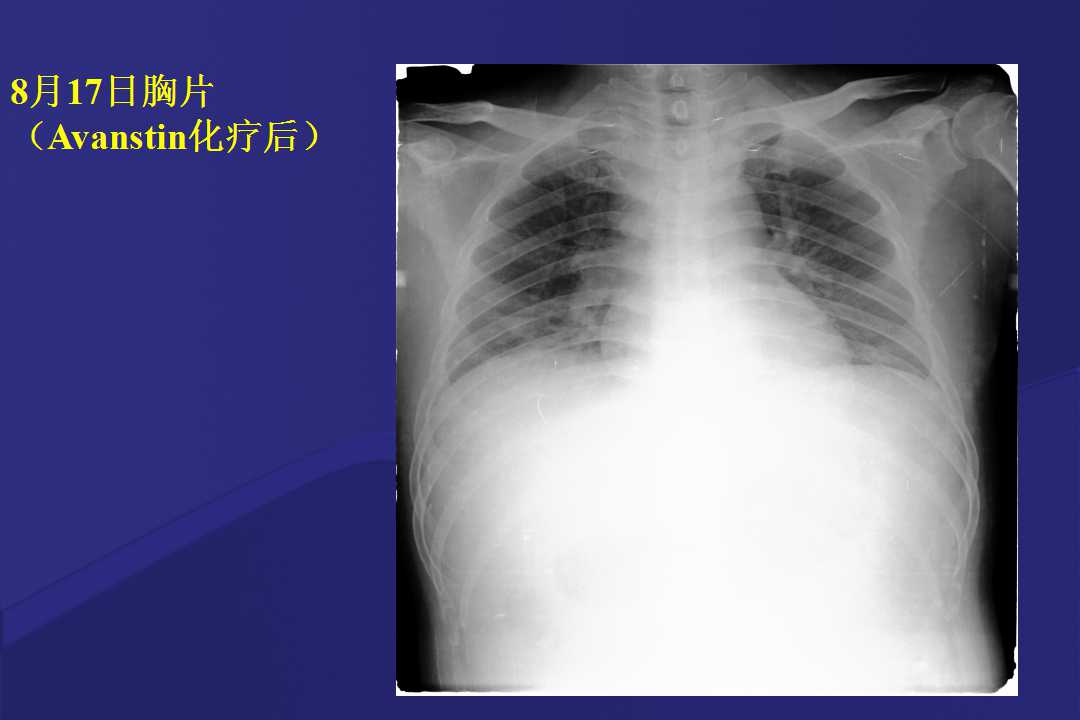

血液疾病患者肺部并发症影像学表现